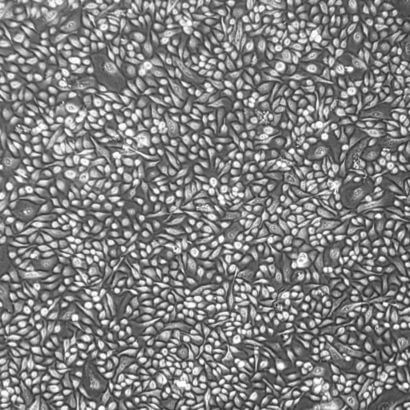

Lifeline® normal Human Mammary (Breast) Epithelial Cells (HMEC) – female, when grown in Lifeline® MammaryLife™ Medium, provide an ideal serum-free culture model for the study of the stages of breast cancer development, three dimensional culture, carcinogen screening, and other areas of breast research.

Our HMEC are quality tested in MammaryLife™ Medium to ensure optimal morphology and growth over a period of at least 15 population doublings. Lifeline® Female Mammary Cells are a mixed culture of epithelial cells bearing positive markers such as Cytokeratin 14 (myoepithelial), Cytokeratin 8/18 (luminal), and Cytokeratin 19 (luminal subpopulation).